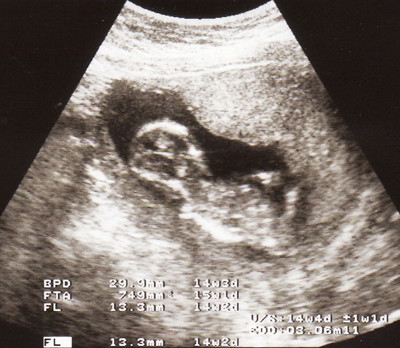

Isteriku disahkan mengandung 🙂